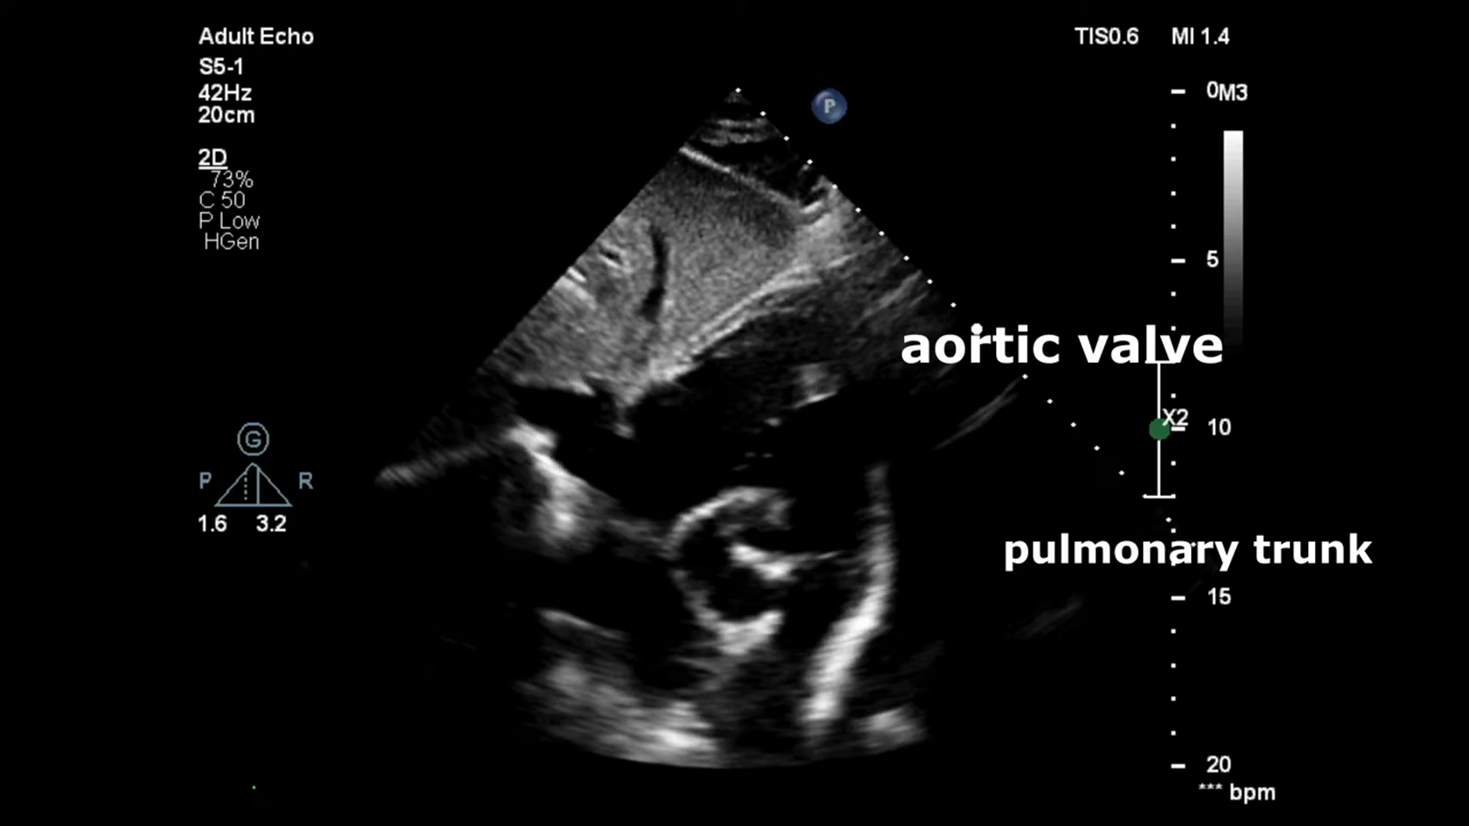

Echocardiography

Echocardiography: 6 mm peri membranous ventricular septal defect with left to right shunting dilated left atrium and left ventricle normal systolic function